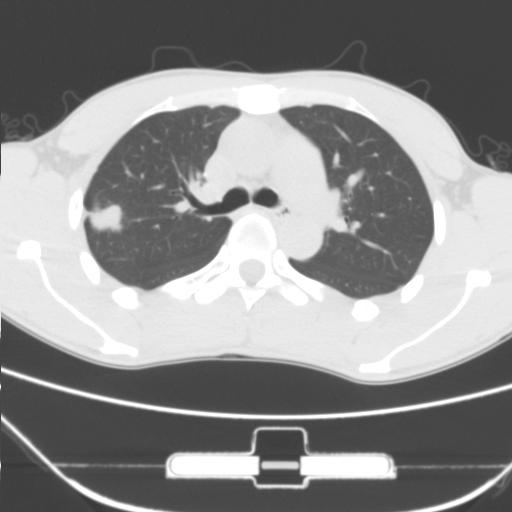

标题: CT25483:肺部病变 请指教

车祸伤者

右肺上叶后段近胸膜下结节样异常密度灶,似见分页及毛刺,考虑右肺上叶周围型肺ca,建议穿刺病理检查

周围型肺ca与炎性假瘤待鉴别。建议穿刺病理检查

缺乏病史,症状体征,但这个孤立结节具备了几乎所有的恶性征象:分叶,毛刺,空泡征,胸膜凹陷征,血管集束。